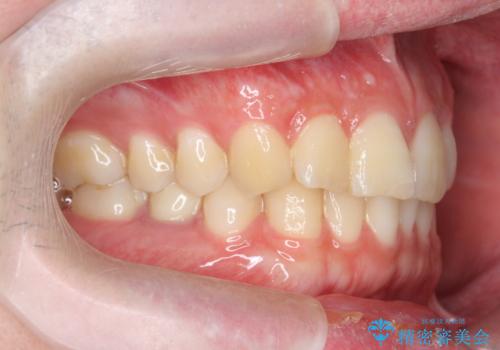

前歯のがたつきをなおしたい マウスピース矯正

- 気になる前歯のがたつきをきれいにしたい。と矯正治療を希望され来院されました。

大きな歯列の乱れはないため、倒れ込んでいる奥歯の傾きの改善、前歯のがたつきを改善する治療を計画します。

見た目が良くなっただけではなく、歯ブラシがしやすくなった!と治療後の歯並びに喜んでいただくことができました。